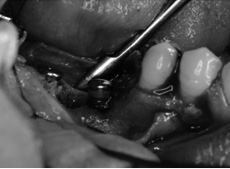

インプラントが露出してしまっています。 骨造成が必要です。 |

骨補填材で埋めます。 |

生体親和性の良い吸収性メンブレン(膜)を設置します。 |

理想的な位置に埋入しました。